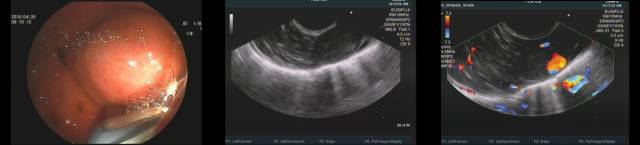

膈肌肿瘤十分罕见,来源于左侧膈肌的肿瘤可压迫胃底形成假SMT,一块看看下面病例,胃镜可见胃底粘膜下半球形隆起,EUS探查见类圆形病灶,超声照影增强后发现病灶供血来源于膈肌(图 C),故诊断为膈肌肿瘤导致的胃底外压。

CT的冠状位和矢状位成像确认膈肌来源肿瘤引起的外压。